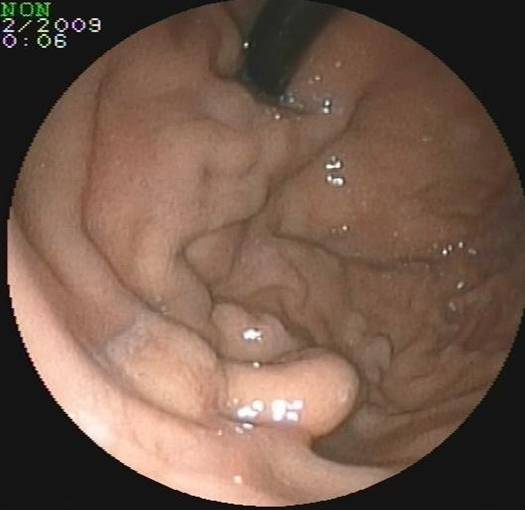

小肠镜检查:胆肠吻合口多发血管扩张,空肠吻合口息肉。

左侧为空肠空肠吻合口

胆肠吻合口迂曲的血管

胆管壁迂曲的血管